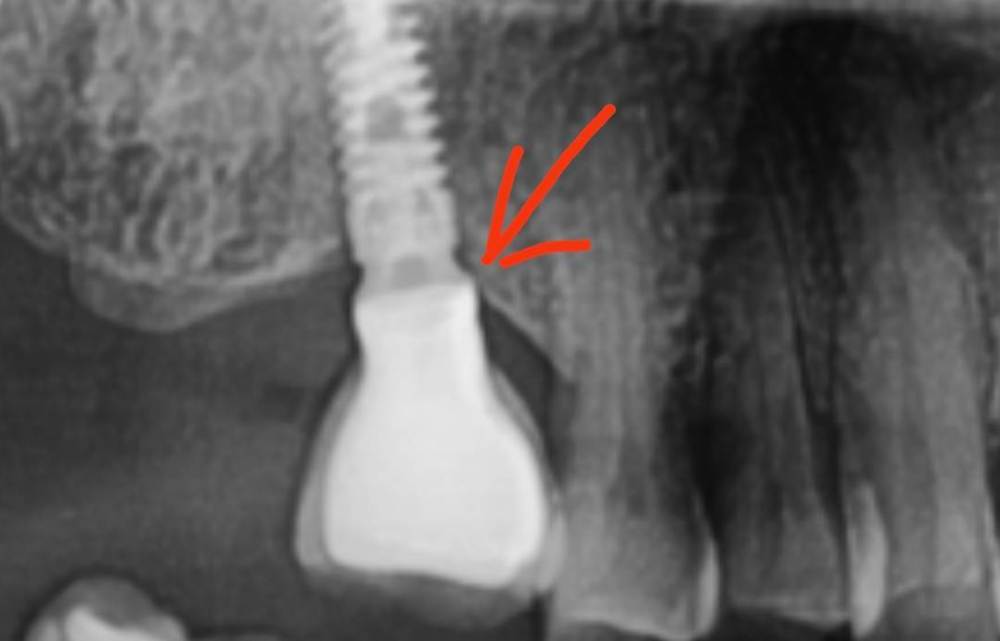

Irouil Опубликовано 8 августа, 2023 Автор Поделиться Опубликовано 8 августа, 2023 Ссылка на комментарий

АнтонТЛТ Опубликовано 8 августа, 2023 Поделиться Опубликовано 8 августа, 2023 Лучше прицельные снимки делать, на таких не рассмотреть ничего. Форум сильно сжимает изображение. Либо кадрировать эти снимки. Почему тибейсы такие короткие используются? Ссылка на комментарий

NazranDantist Опубликовано 8 августа, 2023 Поделиться Опубликовано 8 августа, 2023 (изменено) Вполне возможно упирается в ткани протетика, закручивали с усилием. Только ортопед вам правду расскажет). Если пассивно закручивал протетику, то откручивается по не зависящим от нас причинам, в противном случае- винт под напряжением, либо в тканях упирается, либо контактный пункт. Изменено 8 августа, 2023 пользователем NazranDantist 1 Ссылка на комментарий

Irouil Опубликовано 9 августа, 2023 Автор Поделиться Опубликовано 9 августа, 2023 @АнтонТЛТ думаете короткие ти бейсы могут повлиять? Я сейчас не про пассивность. Лаба работает вообще с большим количеством нареканий, самое смешное в этом то, что она наша)) @NazranDantist согласен, есть риски, что какие-то сели внатяг. Ссылка на комментарий